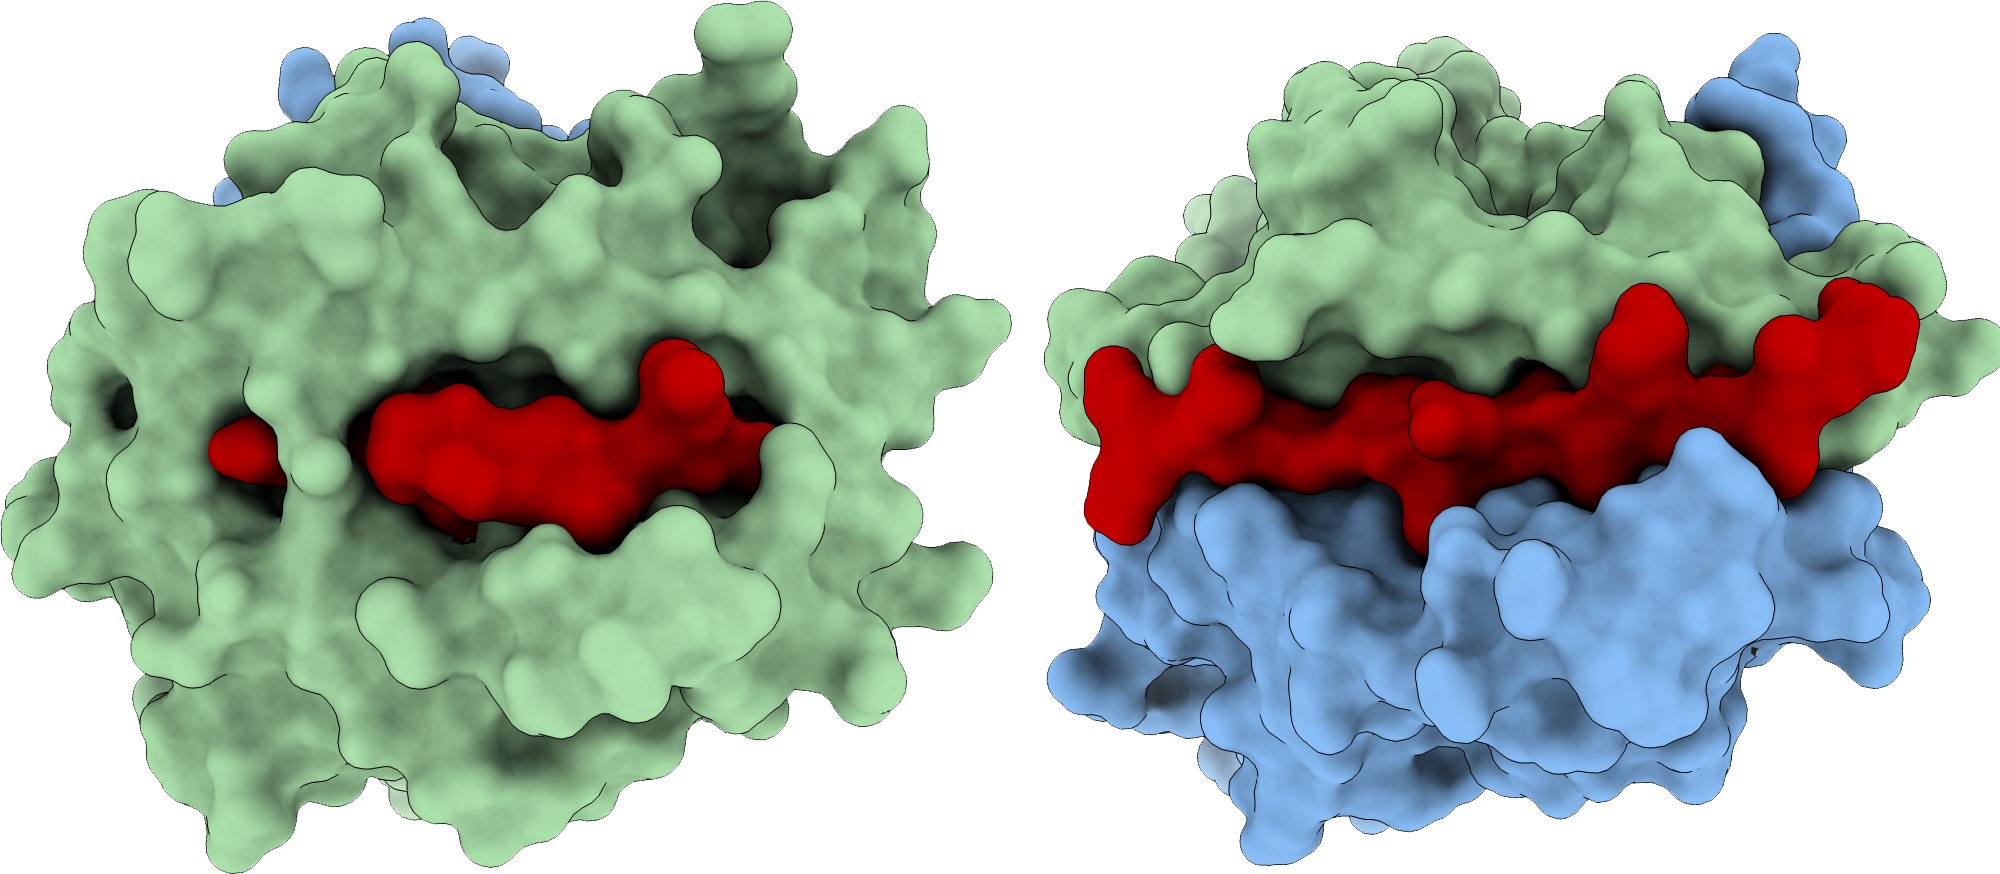

- Structure-based identification of SARS-derived peptides with potential to induce broad protective immunity

- Structure-based Selection of Tumor-antigens for T-cell Based Immunotherapy

- Structural modeling of peptide-HLA complexes presenting a melanoma-associated antigen for cross-reactivity assessment